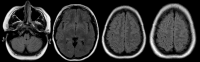

Figure 1

Figure 1. MRI 24 hours after symptoms onset: FLAIR sequence shows hyperintense signals on the left cerebellar hemisphere and in both occipital lobes. cSAH was also observed in left frontal sulci.

Figure 3

Figure 3. MRI performed two months later: shows superficial siderosis secondary to cSAH and resolution of white matter hyperintensities.